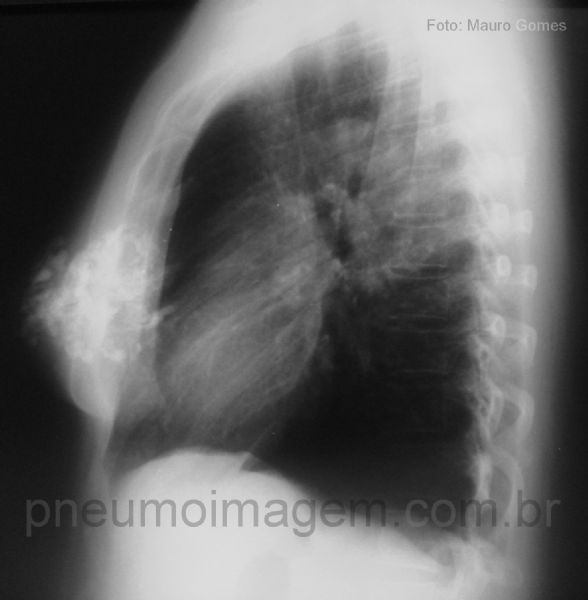

A importância da incidência em perfil pode ser verificada neste caso. Observe os nódulos grosseiros, calcificados, difusos pelos campos pulmonares inferiores.

Sem o estudo em perfil, essas imagens poderiam ser interpretadas erroneamente como nódulos calcificados nos pulmões.

A incidência em perfil esclarece essa questão. Trata-se nódulos com calcificação "em pipoca" localizados nas mamas, que podem ser encontrados no fibroadenoma mamário.

Geralmente assintomático, constitui-se em achado radiológico em pacientes de

maior faixa etária.